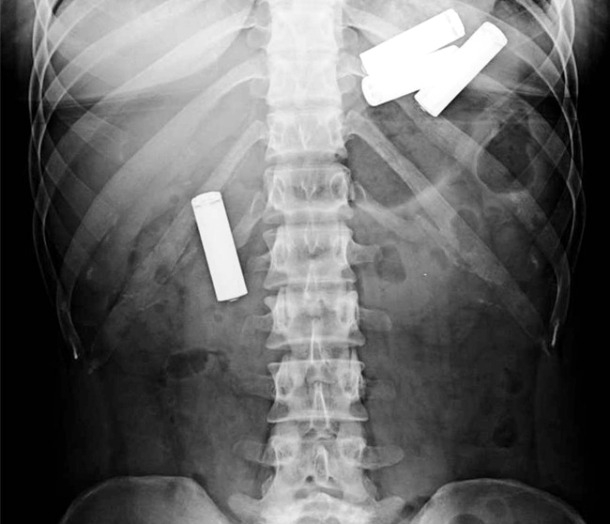

Среди проглоченного оказались: сто пятьдесят три гвоздя, сто сорок монеток, орехи, болтики и батарейка, магниты, винты и прочие железные мелочи. Врачи провели эндоскопию, введя шланг с камерой прямо ему в желудок, таким образом, они и обнаружили все это. К слову, сам пациент боли в животе с поглощением предметов не связывал. Более того, он постоянно приходил в медицинские центры, но врачи ему правильный диагноз до сих пор не ставили. Уже понадобилось более двухсот сорока эндоскопических процедур, чтобы удалить все инородные предметы.